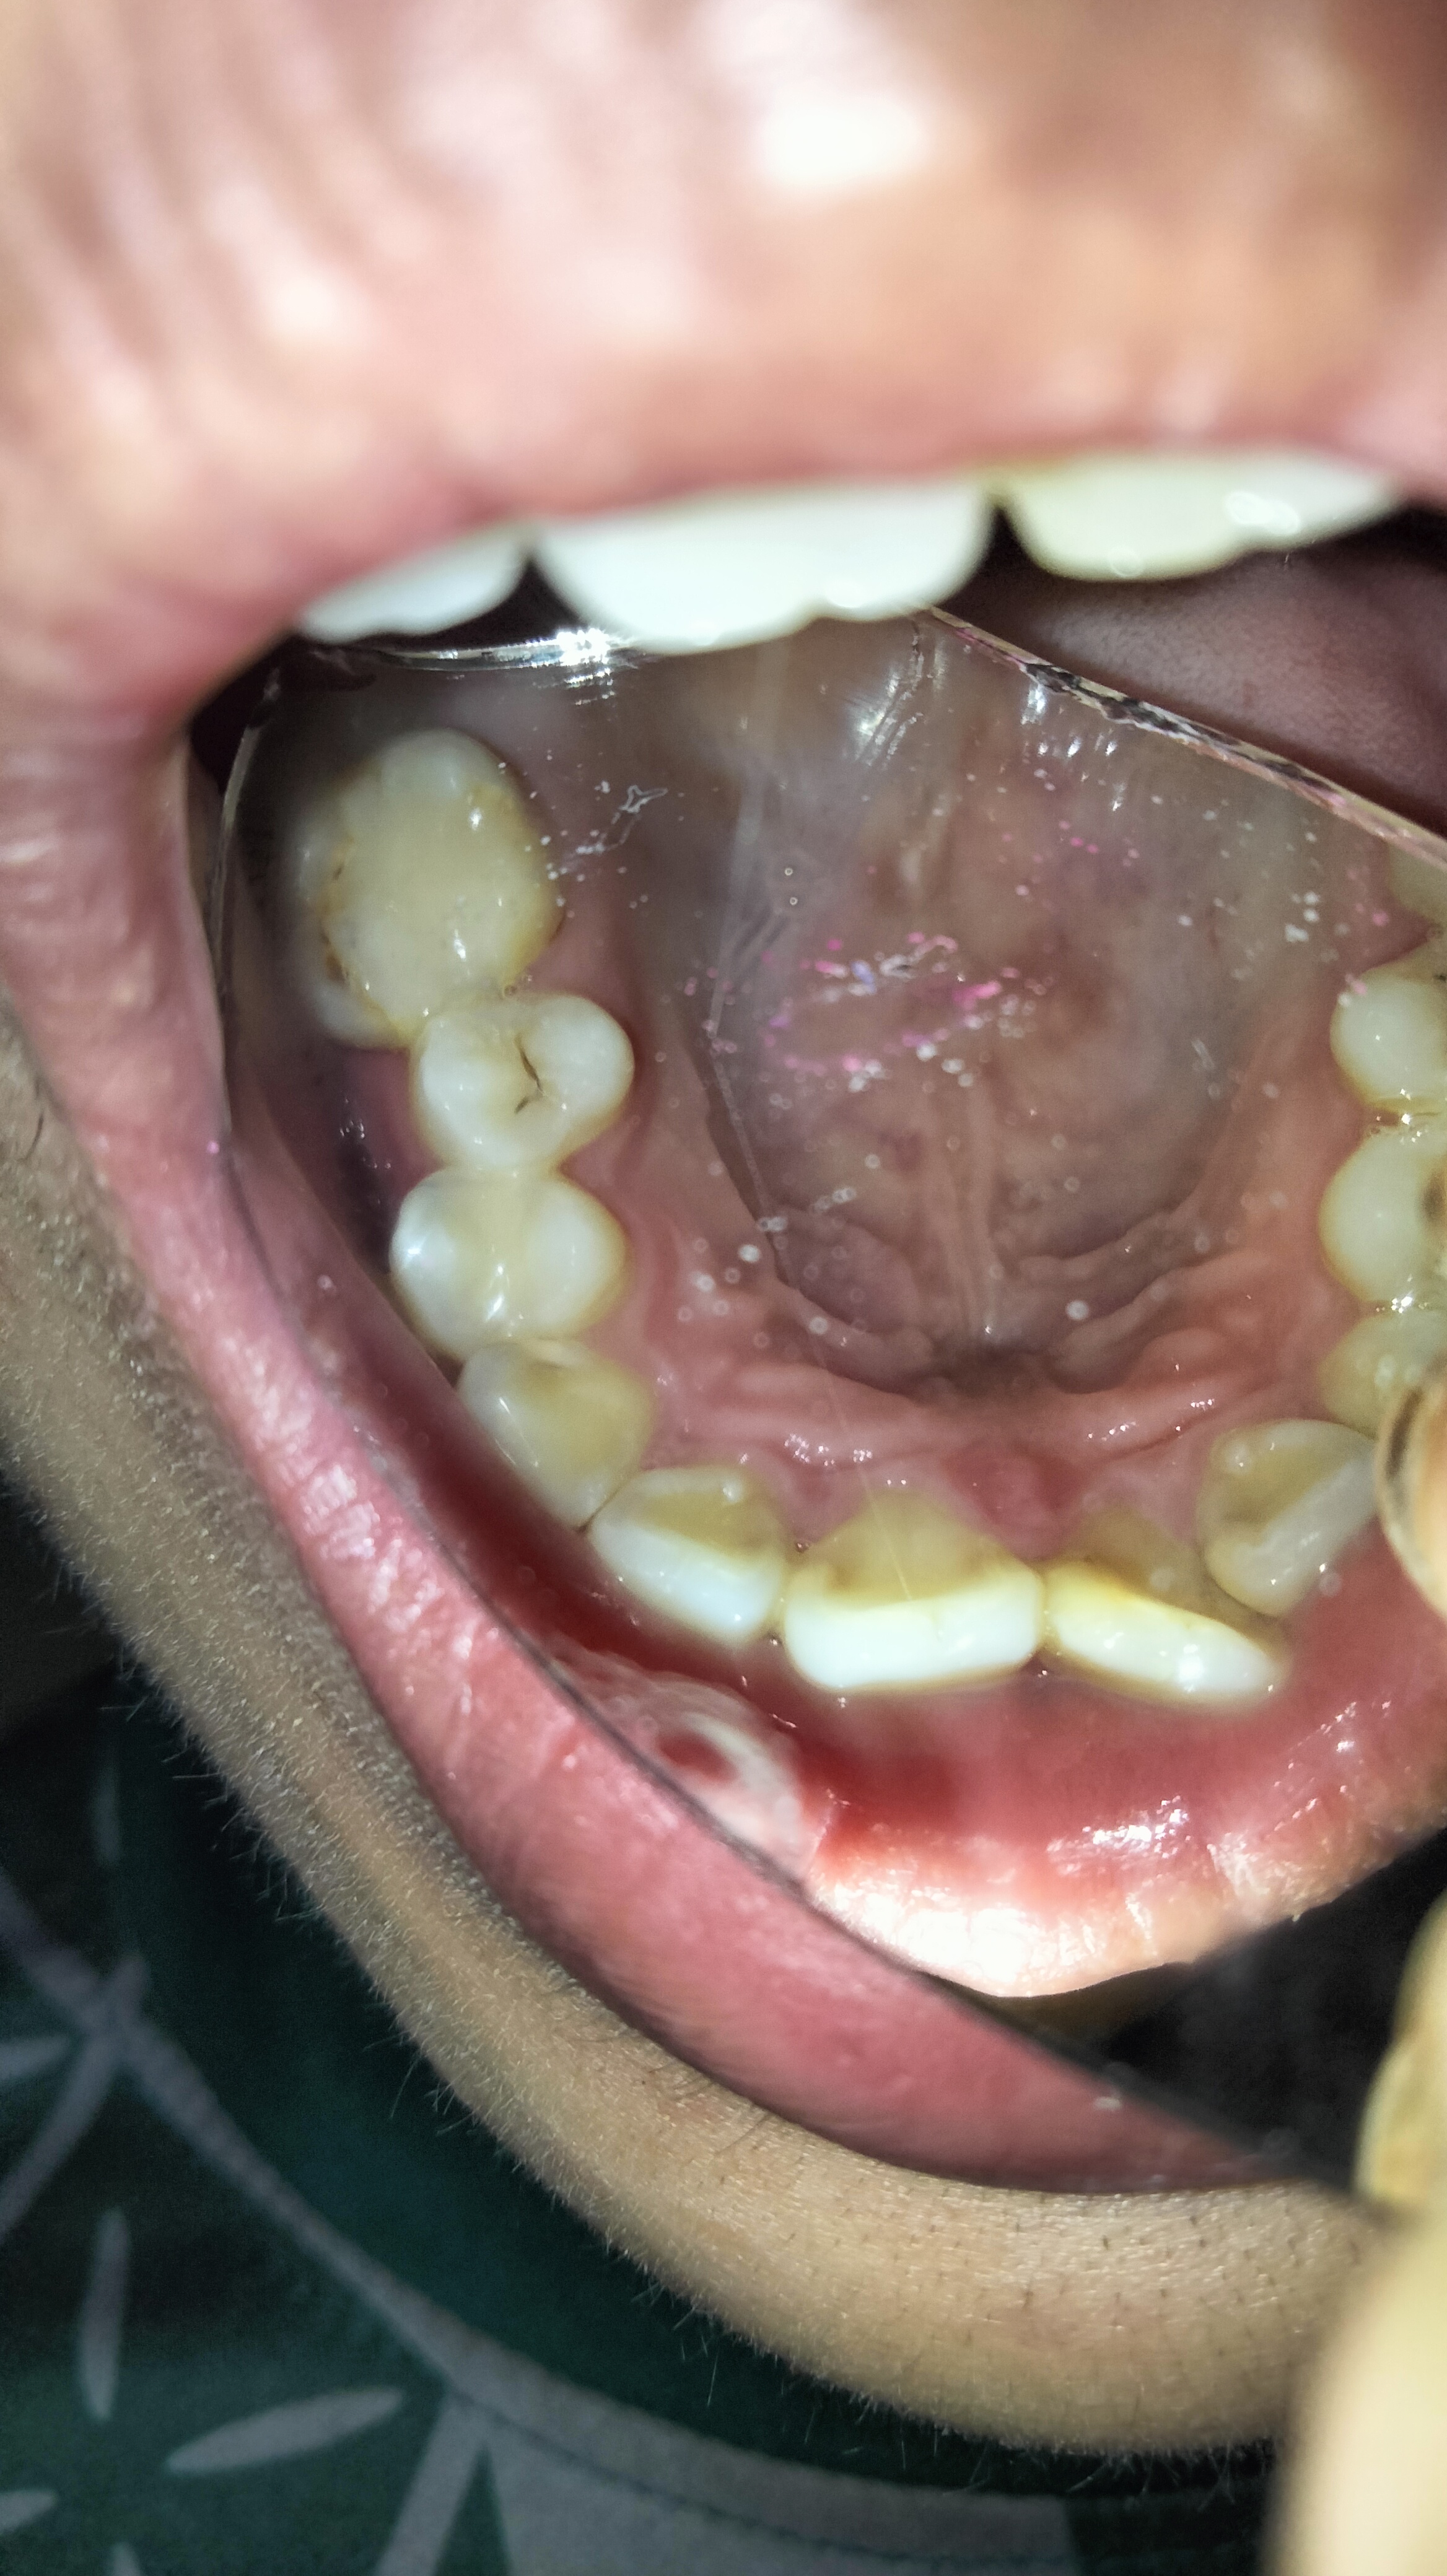

Bác sĩ ơi xem giúp em những cái này cái nào sâu cần trám và không cần ạ e đi khám thấy nói trám hết trơn 14 cái e lo quá giúp em với

Chào e. Chỉ răng có lỗ sâu mới cần trám. Còn sâu bề mặt ngà răng chưa trám nhé

Không trám hết đâu em. Em ra phòng khám răng để được khám tư vấn kỹ hơn

Dạ bác cho e hỏi 5 răng cửa của e có phải sâu không ạ

Đi họ bảo sâu 5 cái đó lun😭